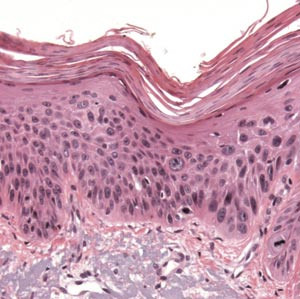

Aktinisk keratose har forskjellige presentasjonsformer. Lesjonen er begrenset til epidermis og gjenkjennes ved tap av cellenes polaritet, cytologisk atypi og enkelte mitoser (e-fig 1, fig 2, fig 3). De atypiske keratinocyttene finnes oftest nær basallaget (e-fig 1), men atypiske epitelceller kan også finnes i andre lag av epidermis når lesjonen progredierer (fig 2, fig 3). På overflaten er de atypiske keratinocyttene dekket av hyperkeratose og parakeratose, noe som gjør at epidermis blir fortykket når lesjonen blir mer avansert.

Grensen mellom dysplastiske og normale keratinocytter er ofte skarp. De atypiske keratinocyttene danner ofte tappformede nedvekster fra basallaget som kan gå over i svettekjertler og hårfollikler uten gjennomvekst av basalmembranen. De vanligste formene er atrofisk, hypertrofisk, bowenoid og lichenoid. Den atrofiske varianten har ofte lettere atypi, mens den hypertrofiske og den bowenoide er karakterisert ved grov atypi og manglende polaritet i hele epitelet, som ved cancer in situ. Bare manglende infiltrasjon gjennom basalmembranen skiller hypertrofisk og bowenoid form fra plateepitelkarsinom (fig 4).